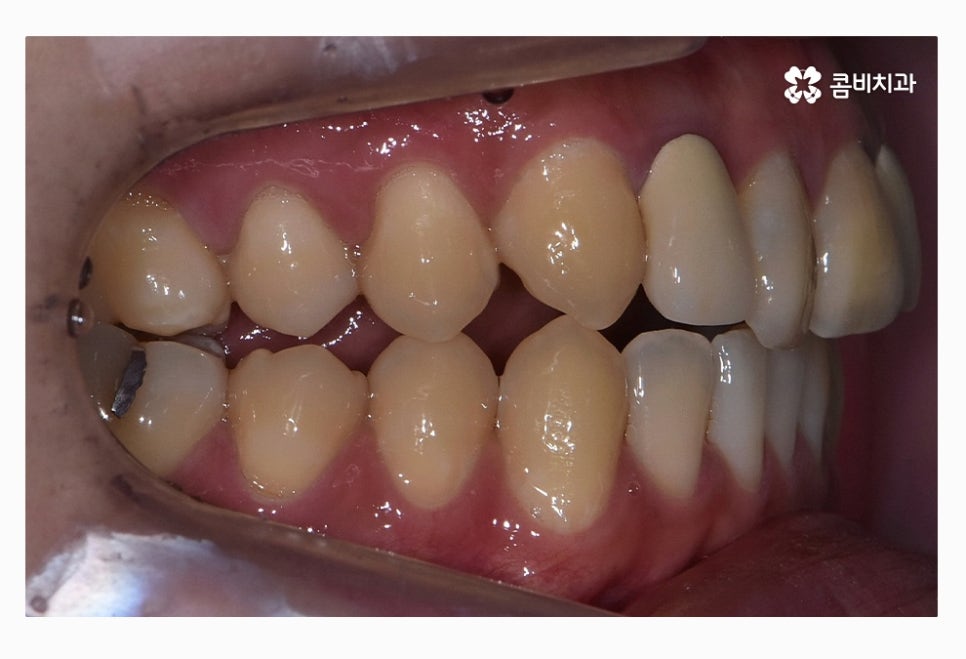

위 환자분의 경우 치열을 볼 때 정면에 비해서 측면으로 보면

앞니가 삐뚤어져 있는 것이 눈에 띄며 교합이 맞지 않아

윗니가 아랫니를 정상적으로 덮지 못하고 있는 상태이며

치아의 이동 공간 및 교합 등으로 볼 때 비발치로

치료가 가능했던 사례라고 할 수 있어요.